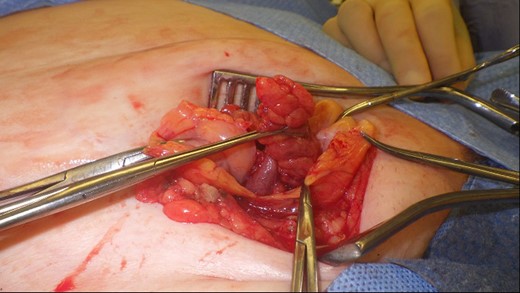

This 82-year-old lady presented with a sudden painful right sided groin swelling not previously noticed. She had no features of obstruction and was opening her bowels and not vomiting. Her medical background included left sided femoral hernia repair in 2005, coronary artery bypass graft and bilateral total knee replacements. On examination her abdomen was soft with the presence of a tender, irreducible swelling in the right groin, inferolateral to the pubic tubercle. She had good bowel sounds and there was stool present in the rectum on PR examination. A full set of blood tests demonstrated no abnormality. A CT abdomen and pelvis demonstrated an incarcerated right sided femoral hernia containing an 8 mm long inflamed appendix with a small amount of localized free fluid and inflammation indicative of De Garengeot’s hernia with underlying acute appendicitis (Fig. 1). The hernia sac diameter measured 2 mm on CT scan. She was taken to theatre for an open Lockwood repair of her femoral hernia and an appendicectomy. Following an initial Lockwood incision over the lump, dissection was performed down to the hernia sac also exposing the inguinal ligament (Fig. 2). The tightness of the femoral ring made mobilization of the appendix difficult. By partially incising the inguinal ligament superior to the femoral ring, the appendix was freed, and on inspection showed inflammation particularly towards the tip (Fig. 3). The caecum was then reduced and the inguinal ligament was repaired with non-absorbable suture. The femoral hernia was then repaired with a small funnel of ultrapro mesh. Appendicectomy was then performed in the usual fashion via the Lockwood incision leaving a slightly longer stump than usual (Fig. 4).

Excised appendix specimen with a slightly longer than usual appendix stump.

The patient had an uneventful recovery and was discharged on the second postoperative day. Subsequent histopathology of the appendix specimen demonstrated serosal inflammation throughout the appendix with partial fibrotic obliteration of the appendix lumen. No formal follow-up was organized and to date there have been no complications following surgery.